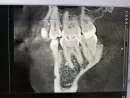

На снимке увидела светлое пятно около корня. Уже 2 зуба удалили из-за кисты с правой стороны. Очень страшно, что и с этой стороны проблемы. Прикладываю панорамный снимок после операции и часть 3-d снимка перед удалениями, на котором видно это пятно.

Может ли быть это причиной болей? Это киста?

На данном снимке киста не определяется, необходимо оценить 3-d снимок во всех проекциях. Вероятнее всего появление боли связано с удалением. Рекомендуем обратиться к стоматологу-хирургу, для осмотра полости рта и исключения неблагоприятных осложнений.